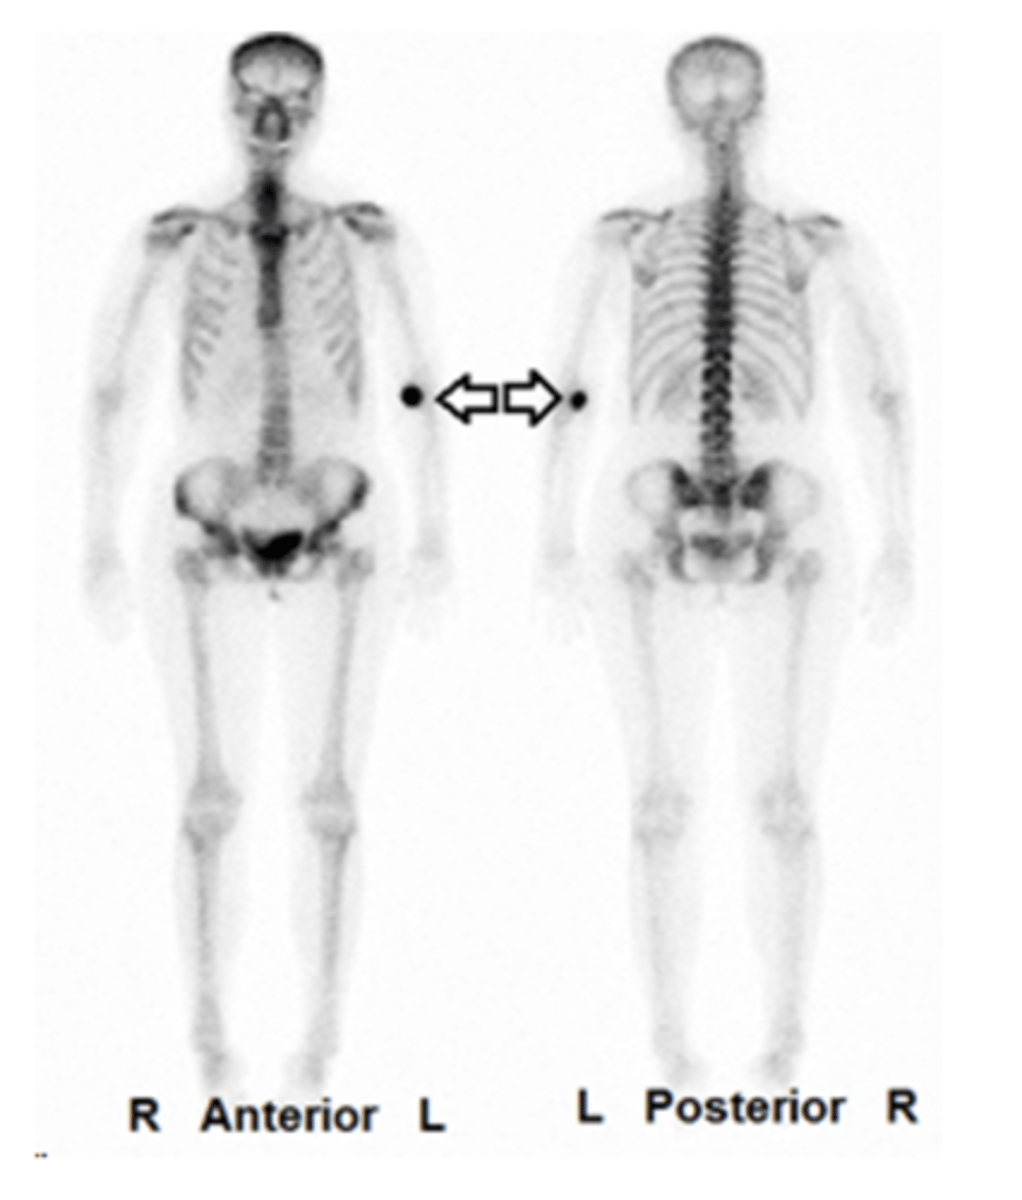

On the following image, what is the most likely cause for the area of increased activity?

this is where the patient was injected and some radiopharmaceutical is left at the injection site

On the following image, what is the most likely cause for the increased activity?

the hand on the left side of the screen is on an arm where the radiopharmaceutical was injected into an artery instead of a vein